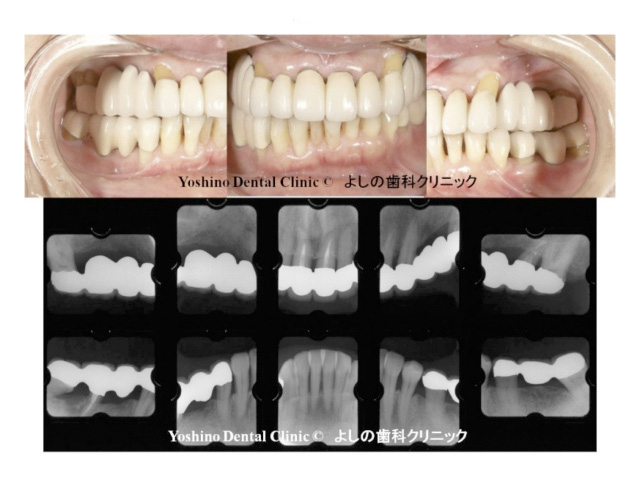

この様に、専門医による治療により保存が困難な歯を抜かずに治療も可能です。もちろん、我々歯周病専門医は、年間数百症例のインプラント治療も行いますが、我々は歯科医師ではあるけれども、決してインプラント医師ではないので歯の保存が可能であれば積極的に歯を守る治療を行うのが我々の使命だと考えております。どうしても、歯の保存・維持が困難と判断され、噛み合わせの機能的障害及び審美的障害が生じる恐れがある場合のみインプラント治療をご提案させていただいております。

また、歯周病専門医だから歯の根の病巣治療、歯の審美歯科治療や歯の矯正治療等は出来ないと云うことではありません。歯周病専門医は、専門医自身が全ての歯科分野の治療領域を高いレベルで治療が行えないと歯周病専門医になることは難しいのです。その中でも特に、歯周病治療、予防歯科、インプラント治療に関しては、エキスパートとして訓練を積んでいます。